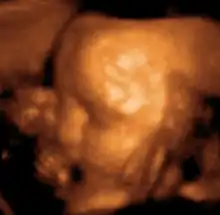

طُور تخطيط الصدى التوليدي في أواخر خمسينيات القرن العشرين وستينياته على يد السير إيان دونالد، وهو يُستخدم بشكل شائع في أثناء الحمل لمتابعة تطور الجنين ومظهره. يمكن استخدامه لكشف الكثير من الحالات المؤذية للأم و/أو المولود التي تبقى دون تشخيص أو يتأخر تشخيصها بغياب التصوير بالأمواج فوق الصوتية. يُعتقد حاليًا أن خطر ترك هذه الحالات دون تشخيص أكبر من الخطر الصغير المحتمل المرتبط بالتعرض للأمواج فوق الصوتية. لكن استخدامه للأغراض غير الطبية مثل مقاطع الفيديو والصور «التذكارية» الخاصة بالجنين غير محبذ.[3]

صورة ثلاثية الأبعاد لجنين عمره 29 أسبوع.